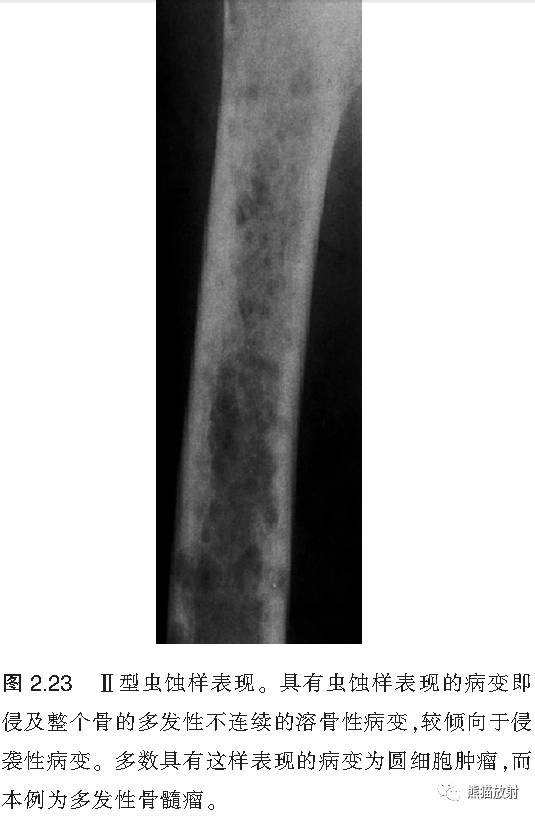

↓ 多发性骨髓瘤

II:虫蚀样